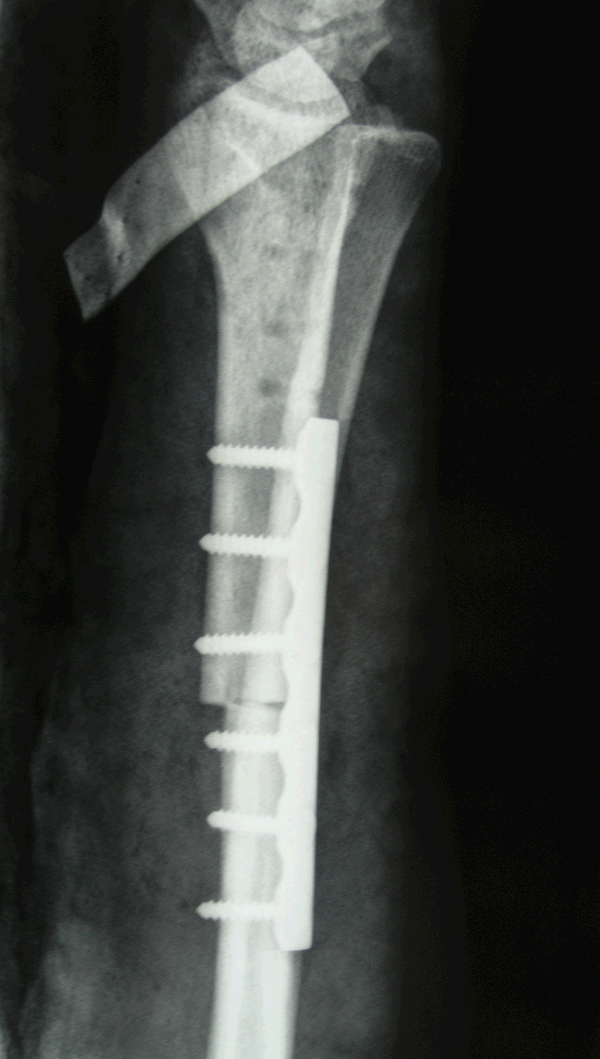

4.病例4:女 35岁, 右桡骨远端骨巨细胞瘤(Campanacci Ⅲ级),行瘤段广泛切除异体半关节移植术

图 16 术后X线片 a:正位

b:侧位